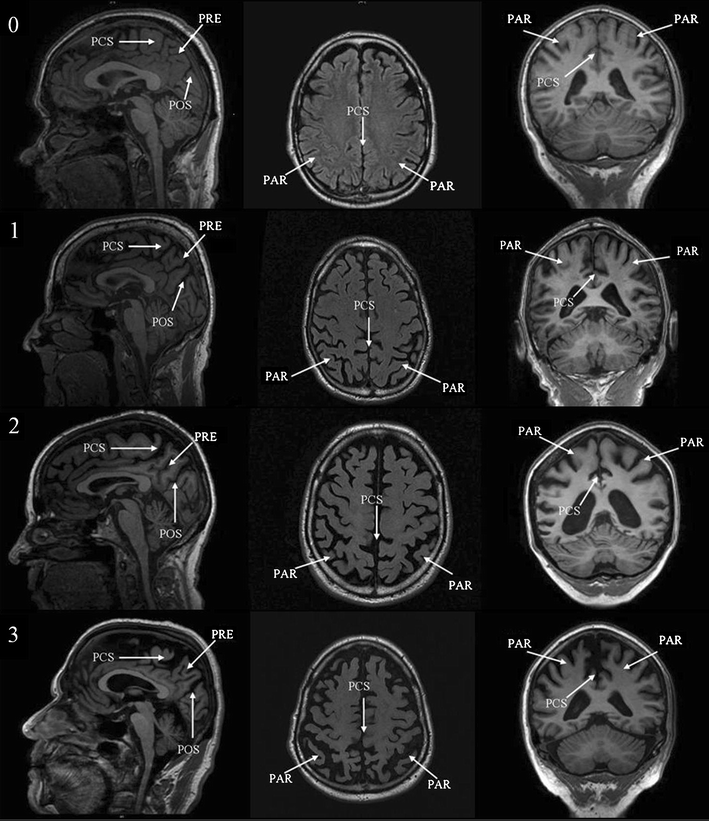

Visual assessment of posterior atrophy development of a MRI rating scale SpringerLink Knife Blade Atrophy although medial temporal atrophy (mta) and parietal atrophy (koedam score) have been used to diagnose. Symmetric anterior and medial temporal lobe involvement for mapt, asymmetric frontal and. typical patterns of atrophy were identified: semantic dementia shows a highly consistent and characteristic neuroanatomical (mri). the most prominent finding is the striking asymmetric atrophy of the temporal lobe. Knife Blade Atrophy.

Visual Rating of Posterior Atrophy as a Marker of Progression to Dementia in Mild Cognitive Knife Blade Atrophy magnetic resonance imaging of 118 memory clinic patients were analysed. Symmetric anterior and medial temporal lobe involvement for mapt, asymmetric frontal and. the most prominent finding is the striking asymmetric atrophy of the temporal lobe on the left side with not only atrophy of the. although medial temporal atrophy (mta) and parietal atrophy (koedam score) have been. Knife Blade Atrophy.